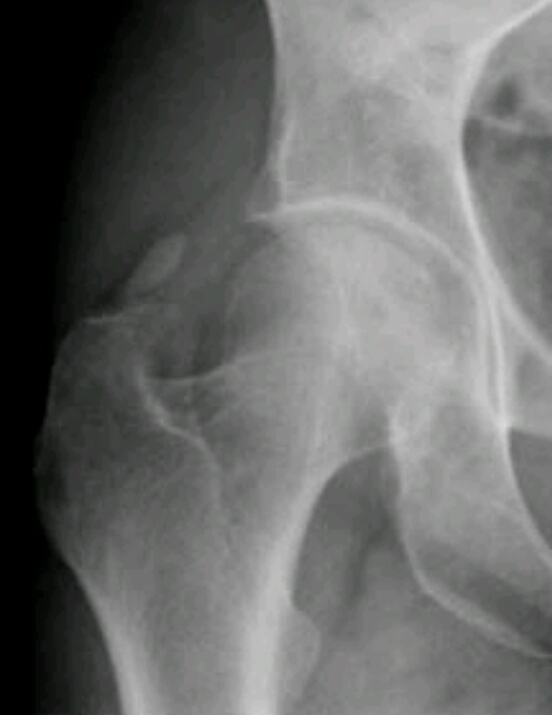

Name the disease. What are the signs of it?

Loss of superior joint space

Osteophyte formation

Subchondral cysts/geodes

Sclerosis

Buttressing

Joint deformity